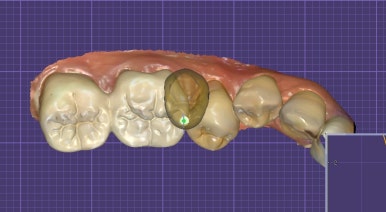

오늘은 오래 사용하던 크라운이 깨져 내원하신 환자분께

지르코니아 재보철을 하루 만에 진행한 사례를 소개해드릴게요.

이번 환자분 역시 기존 크라운이 레진계열 소재로 제작돼

시간이 지나면서 파절된 상태였습니다.

![]() |